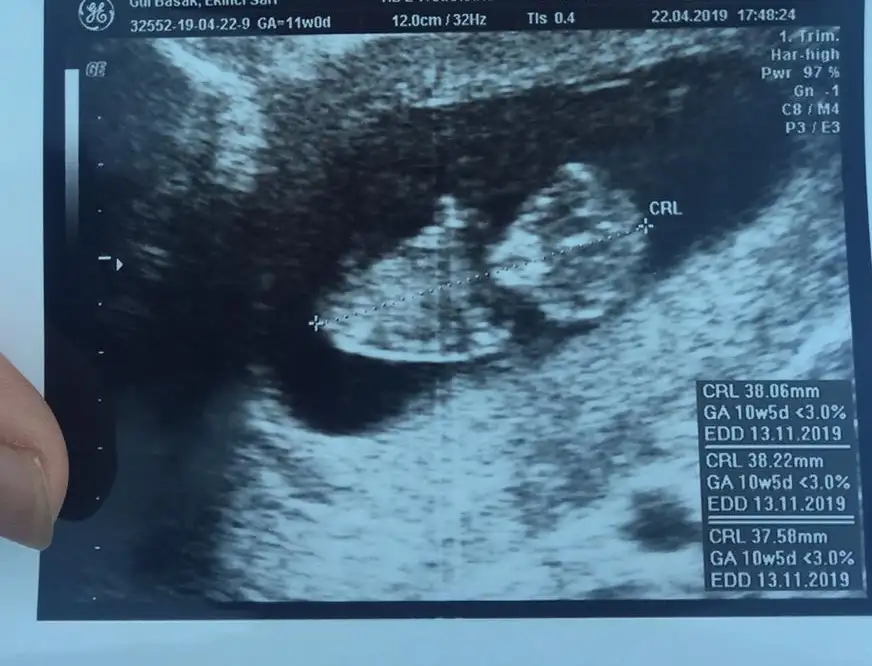

Fotosu yok mu kuzunun? Gün olarak paralel olabiliriz seninle kendi bebisimi görmüş gibi olurum valla 😍

Eklentiler

• C01A609C-470F-4702-AA19-13C9406E7DA1.webp

C01A609C-470F-4702-AA19-13C9406E7DA1.webp

27,3 KB · Görüntüleme: 58

• D8130AD8-8DAF-4C73-980A-7B2C7B525709.webp

D8130AD8-8DAF-4C73-980A-7B2C7B525709.webp

33,5 KB · Görüntüleme: 63